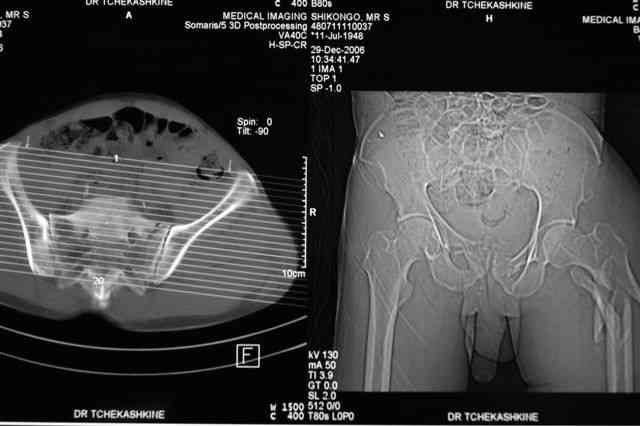

Я помню технику транссакральной фиксации тазового кольца длинными 5 мм Шанцами - повреждения типа В, в этом же случае задний отдел тоже вовлечен

т.е комбинированная нестабильность, поэтому вопрос - достаточно ли только двух Шанцев для стабилизации таза? Что вы думаете об anterior Right SI joint plating + tension band plating from the back.?

PS после фиксации бедра под Эопом посмотрел инлет и аутлет проекции, насколько репонируемо смещение правой половины таза *невооруженными*

руками - никаких шансов улучшить позицию иначе бы конечно воспользовался длинными Шанцами сразу после бедра.

Элегантная фиксация, поздравляю.Но ваш случай : одноплоскостная горизонтальная нестабильность Tyle B2.2 отличен от представленного мной - у

моего больного + вертикальная нестабильность за счет повреждения правого крестцово-подвздошного сочленения и перелома заднего отдела подвздошной

кости- С2 тип. Поэтому и возникла дилемма : выбор оптимальной фиксации заднего отдела:

По-поводу фиксации таза спонгиозными винтами. Данный способ все-таки показан для фиксации повреждения крестцово-подвздошного сочленения или переломов крестца. Мне кажется, что в данной случае ситуация иная - имеется перелом "основания" крыла подвздошной кости (в который вовлечена и поверхность, составляющая крестцово-подвздошное сочленение). Не уверен, что фиксация данного повреждения (и заднего полукольца) винтами будет стабильной, так как именно на уровне 1-2 крестцовых позвонков (где обычно вводят винты) линия перелома уходит в латеральном направлении от крестцово-подвздошного сочленения.

PI>По-поводу фиксации таза спонгиозными винтами. Данный способ все-таки показан

для фиксации повреждения крестцово-подвздошного сочленения или переломов крестца. Мне кажется, что в данной случае ситуация иная - имеется перелом

"основания" крыла подвздошной кости (в который вовлечена и поверхность, составляющая крестцово-подвздошное сочленение). Не уверен, что фиксация данного повреждения (и заднего полукольца) винтами будет стабильной, так как

именно на уровне 1-2 крестцовых позвонков (где обычно вводят винты) линия перелома уходит в

латеральном направлении от крестцово-подвздошного сочленения.

Я просмотрел томограммы и у меня создалось впечатление, что винтам есть за что *зацепиться*. В сочетании с 5 мм Шанц винтами, проведенными через нижне-переднюю ость спереди назад через КП сочленения -стабильность тазового кольца должна восстановиться. - Это , конечно, при условии , что закрытая рнепозиция будет успешной.